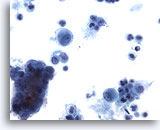

Figure 12

Bronchial wash

Compare the size of the cell cluster with adjacent macrophages and single epithelial cells. 40x

Bronchial wash

Compare the size of the cell cluster with adjacent macrophages and single epithelial cells. 40x

Figure 12

Bronchial wash

Compare the size of the cell cluster with adjacent macrophages and single epithelial cells.

40x

Bronchial wash

Compare the size of the cell cluster with adjacent macrophages and single epithelial cells.

40x